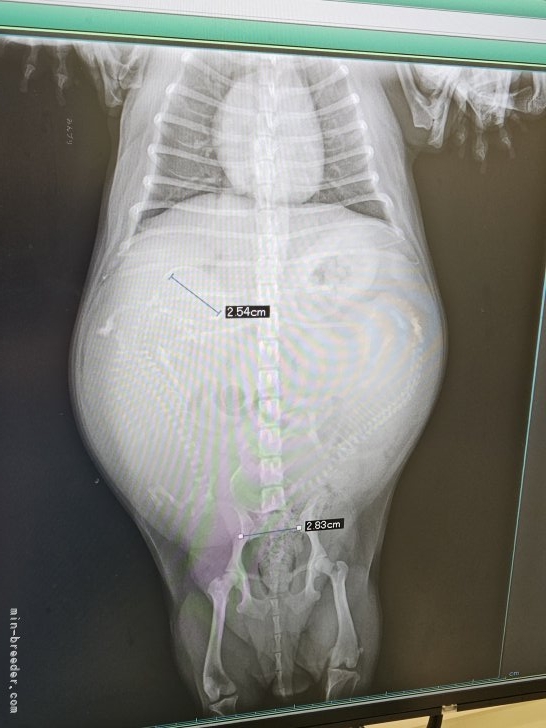

帝王切開前日のレントゲンにて、胎児が2頭と確認しました

レントゲン写真では自然分娩の出産可能と言われました

そうした中、レントゲンを撮り写真を見て、獣医師は自然で行けるよ…と、しかしながら帝王切開を選択しました

帝王切開して出てきた赤ちゃんは140グラム

これは、2.5キロのチワワの自然分娩では確実に難産になるサイズで分娩中、胎児が引っ掛かり死亡するリスク大のサイズでした